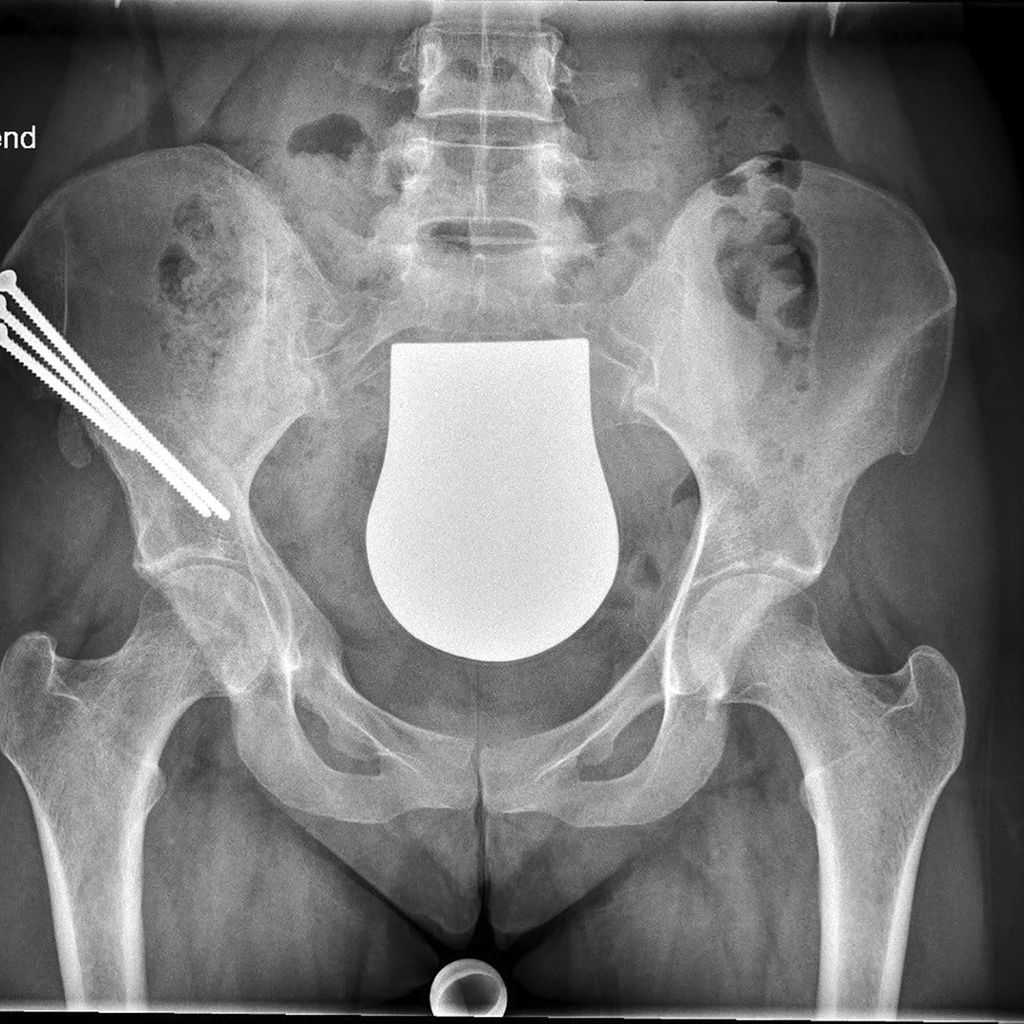

Intraoperative Bildgebung als Fehlerquelle hinsichtlich der Pfannenversion

Die intraoperative Reorientierungs-Position des Pfannenfragmentes auf Basis von Durchleuchtungsbildern in liegender Position stellt derzeit immer noch eine große Herausforderung für jeden Chirurgen dar. Die Ursachen dafür liegen einerseits in der posterior-anterioren Röntgenstrahlrichtung und der geringen Film-Fokus-Distanz der intraoperativen Durchleuchtung im Vergleich zur konventionellen Beckenröntgenaufnahme, andererseits in einer veränderten Beckenkippung im Liegen im Vergleich zur stehenden Position. Diese Faktoren verändern die Darstellung der Pfannenversion intraoperativ. Da aber sowohl eine Unter- als auch eine Überkorrektur der Pfannenversion zu klinisch schlechteren Ergebnissen und in der Folge zu einer erhöhten Arthroserate führt, ist auf die Pfannenversion besonders zu achten.5 Die Verwendung von Schnitt- und Korrekturblöcken könnte hier zukünftig Abhilfe schaffen.

Die Verwendung einer patientenspezifischen Instrumentation (PSI) auf Basis einer 3D-Modell-Planung ist bei knienahen Umstellungsosteotomien in der Orthopädie bereits ein gängiges Verfahren. Dieses Konzept kann nun teilweise auch bei der PAO angewendet werden. Dabei wird das knöcherne Becken präoperativ in der Computertomografie erfasst und am 3D-Modell werden die optimalen Schnittführungen um die Hüftgelenkspfanne geplant. Mittels eigener Software kann das Acetabulum am Monitor auf ein Grad genau in allen Ebenen gedreht werden. Auch eine notwendige Translation des Fragments kann beurteilt werden. In der Korrekturposition des Pfannenfragments können zusätzlich bereits die Positionen und Längen der Schrauben errechnet werden. Auf Basis dieser Planung werden PSI-Schnittblöcke und Korrekturblöcke produziert und für den Eingriff sterilisiert.